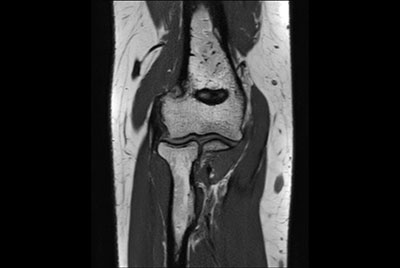

SmartSpeed Traumatic Knee imaging

SmartSpeed 2 min Knee imaging

Knee ACL repair

Knee with lesion

Push-button Knee exam, under 5 minutes

High quality Knee imaging in short scan times

Knee imaging with Compressed SENSE

Knee exam with/without Compressed SENSE

Knee Imaging with Cartilage Assessment

Metal Imaging of the Knee

3D Knee imaging with MSK VIEW

Knee imaging

Comprehensive 3D knee imaging with MSK VIEW